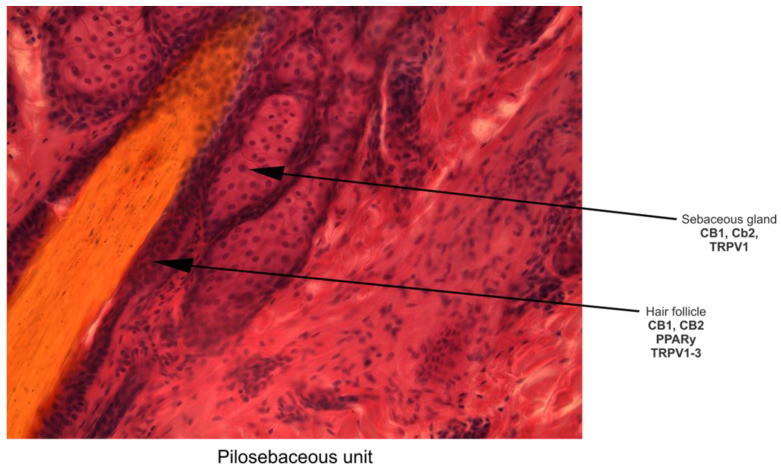

The skin is the largest organ of the human body, extending over an area of 1.5 to 2 m2 in adults [ref. 85]. After the liver, the skin may be considered the largest organ of the human body that metabolizes drugs and xenobiotics [ref. 86]. The skin has a plethora of functions, such as body protection via the cutaneous barrier function, vitamin D synthesis, thermoregulation, and immune defense. Skin disorders affect these physiological mechanisms, oftentimes with systemic effects. It was demonstrated that skin models are valuable tools for organ-specific safety assessment concerning xenobiotic metabolism [ref. 87]. Hence, many synthetic or/and plants-based natural products may be applied to the skin for either local or systemic effects [ref. 85] with the advantage of avoiding first-pass metabolism and improving bioavailability [ref. 7]. Thus, topically applied formulations may target different skin compartments, such as the viable epidermis, known as the key target region for the majority of topical products [ref. 85]; dermis; hypodermis; or skin appendages, such as pilosebaceous units, sweat glands, and nails, while transdermal drug delivery (TDD) targets systemic circulation [ref. 85]. Hence, drug delivery into and across the skin remains challenging [ref. 88].

The skin functions as an interactive network, consisting of physical/mechanical, chemical, microbiological, and immune barriers [ref. 89]. The main components of the mechanical barrier in the skin are the stratum corneum, the tight junctions in the interfollicular epidermis, and pilosebaceous units [ref. 88]. Pilosebaceous units are important routes for both localized and systemic drug delivery, especially for topical liposomes [ref. 90] that are known to be appropriate as drug delivery systems even for phytocannabinoids [ref. 7]. Moreover, endocannabinoids are known to exert an important regulatory role in the biology of skin appendages [ref. 31]. CBD, a skin-permeable phytocannabinoid that has become popular in therapeutic skin products, has been discovered to have a permeability that depends on the vehicle solutions and pH of the environment, which affects its skin permeation rate and skin retention. This knowledge was obtained from in vitro research employing assays that are based on artificial membranes. [ref. 91]. Thus, CBD may have a suitable skin permeability for the development of dermatological or cosmetic applications [ref. 91]. CBD is known as a highly effective sebostatic agent that exerts its anti-inflammatory effect on human skin sebocytes [ref. 92] and on human cultured sebocytes [ref. 30]. CBD, CBN, and THC were bioaccumulated and detected using liquid chromatography–tandem mass spectrometry (LC-MS/MS) in a keratinized matrix of hair and nail samples obtained by noninvasive collection from Cannabis users, with significantly higher concentrations in fingernails than in toenails and hair [ref. 93]. CBD is also known to emphasize antioxidant potential by increasing the expression of the main endogenous antioxidant system, superoxide dismutase (SOD), and glutathione peroxidase (GPx) [ref. 27]. Thus, CBD is one of the most effective protectants against UVA radiation [ref. 26], protecting keratinocytes against the effects of UVA/UVB radiation by reducing lipid peroxidation products and counteracting oxidative stress [ref. 46]. CBD is also involved in wound healing [ref. 32]. Two endocannabinoids, anandamide and 2-arachidonoylglycerol, suppressed proliferation, induced apoptosis, deregulated the expression of cytoskeletal proteins (i.e., cytokeratins), upregulated lipid synthesis, and selectively activated the mitogen-activated protein kinase (MAPK) signaling pathway in human eccrine-sweat-gland-derived immortalized NCL-SG3 model cells; the overexpression of endocannabinoids levels helped manage certain sweat-gland-derived disorders, including tumors, and this was characterized by increased proliferative rates [ref. 31]. Generalized and focal hyperhidrosis or excessive sweating affects the quality of life for almost 5% of the world’s population [ref. 94]. Excessive sweating may be improved immediately after using CBD [ref. 94] and by drop administration and the inhalation of THC, which reduced the volume of sweat [ref. 95]. At the dermal level, Gerasymchuk et al. demonstrated that several pCBs exert rejuvenation efficacy and prevent cellular senescence in human dermal fibroblasts, with applications in cosmetics [ref. 32].

The skin, which is the largest organ in the human body and serves as a barrier between the body and the outside world as well as an immunological function, is made up of three layers, the dermis, the epidermis, and the stratum corneum (SC) [ref. 145,ref. 146,ref. 147,ref. 148], as shown in Figure 2 and Figure 3.